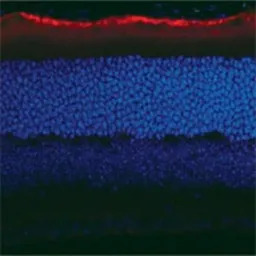

IHC-Fr analysis of mouse retina tissue using GTX13826 RPE65 antibody [401.8B11.3D9].